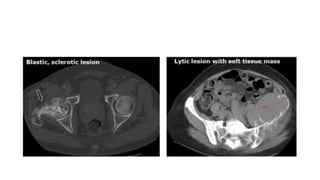

Bone lesions

• Bone scan, PET scan or plain films are not considered adequate imaging

techniques to measure bone lesions.

• Lytic bone lesions or mixed lytic-blastic lesions, with identifiable soft tissue

components, that can be evaluated by CT or MRI can be considered as

measurable lesions if the soft tissue component meets the definition of

measurability described above.

• Blastic bone lesions are non-measurable.